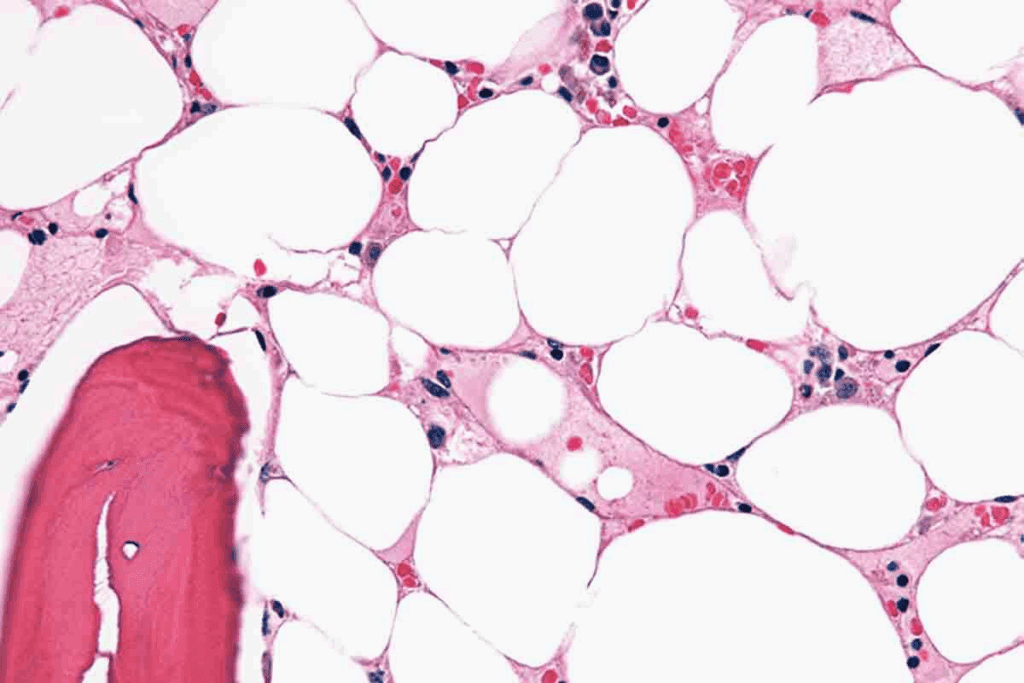

Bone Marrow Biopsy and Aspiration

A bone marrow biopsy and aspiration are key to confirming aplastic anemia. These take a bone marrow sample from the hipbone or sternum for study.

The bone marrow biopsy findings in aplastic anemia typically show:

| Characteristic | Normal Bone Marrow | Aplastic Anemia |

| Cellularity | Normal or increased cellularity | Hypocellularity, with a significant reduction in blood cell precursors |

| Blood Cell Precursors | Presence of various stages of blood cell development | Reduced or absent blood cell precursors |

| Fat Cells | Some fat cells present | Increase in fat cells, replacing the bone marrow space |

“The diagnosis of aplastic anemia is confirmed by the presence of pancytopenia and a hypocellular bone marrow.” –

Aplastic Anemia Foundation